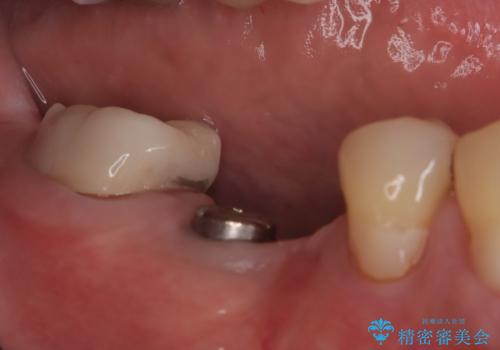

- 奥歯の欠損をインプラントで治療したいと来院された患者様です。

骨の状態が安定するまで待機したのち、インプラントを埋入しています。

スクリューリテインにて上部構造を連結しています。